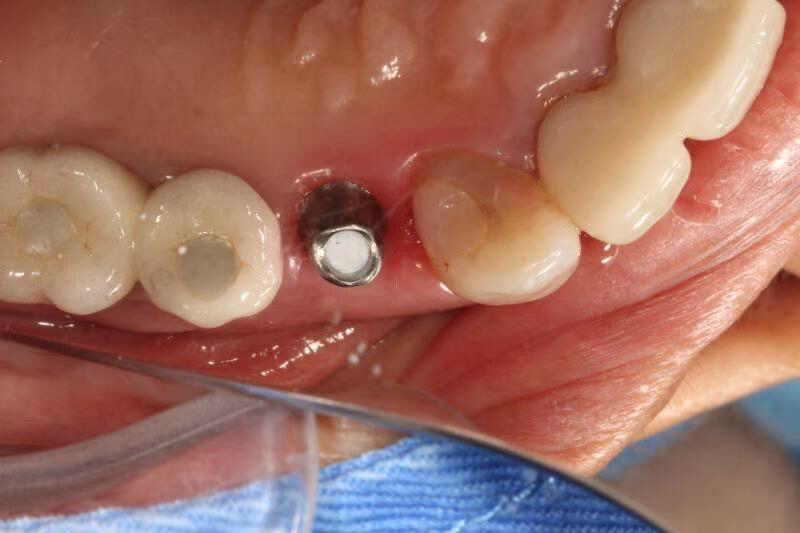

患者女,右上4号牙根管治疗后桩核冠修复,因进食硬物导致桩核冠脱落,未及时处理,导致残根无法修复,从CT上看,牙槽骨高度尚可,所以选择了即拔即种的治疗方案,且术中植骨盖膜、上愈合基台,为患者节省了就诊次数,提前了戴牙时间。